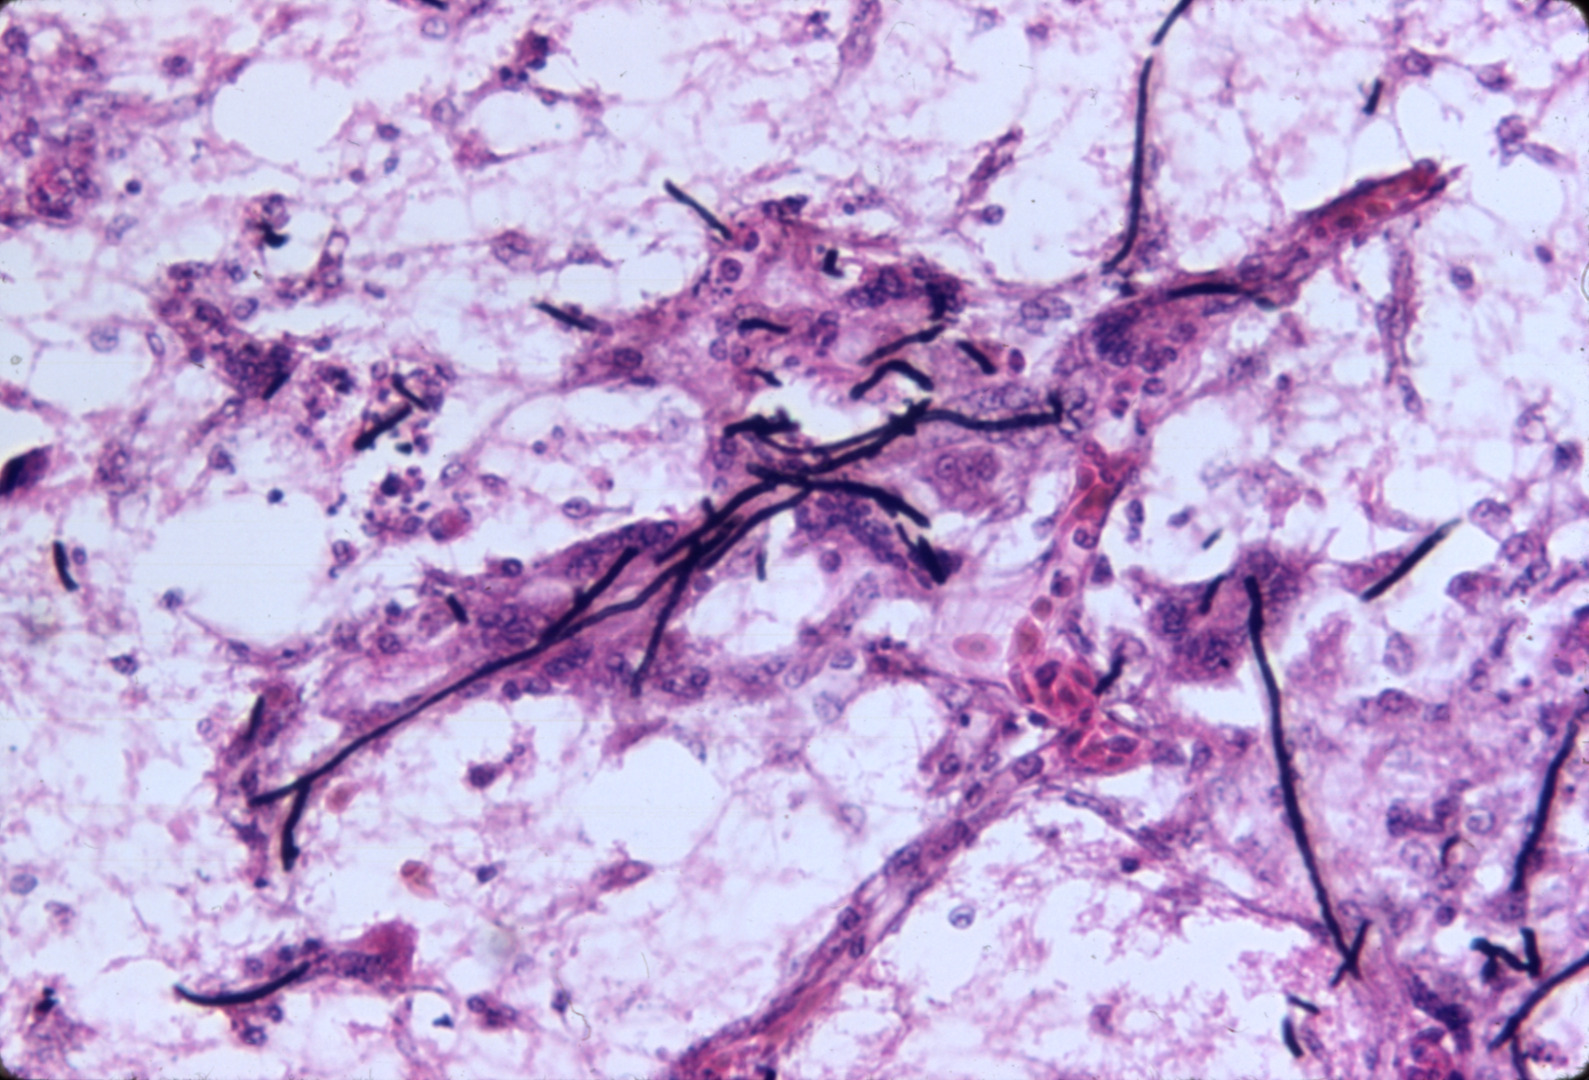

Aspergillosis-dactylariosis (slide study set no. 9)

Poultry--Diseases Aspergillosis

Slide Study Set #9, Aspergillosis-Dactylariosis (includes 24 color slides), 1978